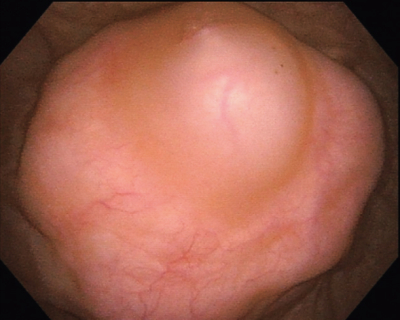

尿所見:蛋白(-)、糖(-)、潜血(-)。血液所見:赤血球 480 万、Hb 13.9 g/dL、Ht 41 %、白血球 4,400、血小板 24 万。血液生化学所見:総蛋白 6.8 g/dL、アルブミン 4.2 g/dL、 総ビリルビン 0.5 mg/dL、AST 14 U/L、ALT 13 U/L、LD 138 U/L(基準 120~245)、ALP 70 U/L(基準 38~113)、γ-GT 12 U/L(基準 8~50)、尿素窒素 14 mg/dL、クレアチニン 0.6 mg/dL、血糖 88 mg/dL、Na 140 mEq/L、K 4.0 mEq/L、Cl 106 mEq/L。腹部超音波検査で膀胱頂部に腫瘍を認めた。膀胱鏡像、腹部 MRI T2 強調矢状断像及び水平断像を別に示す。入院後、開腹腫瘍摘出術および膀胱部分切除術を施行したところ、病理診断の結果は腺癌であった。